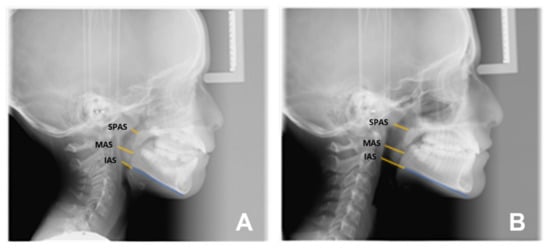

- Airways outcomes: significant changes were found in the width of the upper airways, SPAS (2.21 mm, p = 0.0099), while the improvement in the middle and lower pharyngeal space was not significant, i.e., MAS (1.41 mm p = 0.0786) and IAS (1.64 mm p = 0.1342).

| Sagittal plane analysis: SNA (angle comprised between Sella–Nasion and Nasion point A segments) SNB (angle comprised between Sella–Nasion and Nasion point B segments) ANB (angle comprised between Nasion point A and Nasion point B segments) Vertical plane analysis: Sna-Snp^Go-Gn (intermaxillary angle, angle comprised between the bispinal plane and the mandibular plane) S-N^Go-Gn (mandibular angle, angle comprised between the Sella–Nasion segment and the mandibular plane) PFH/AFH (posterior facial height and anterior facial height ratio) Growth predictors: N-S-Ar (saddle angle comprised between Nasion–Sella and Sella–Articular segments) S-Ar-Go (articular angle comprised between Sella–Articular and Articular–Gonion segments) Ar-Go-Me (gonial angle comprised between Articular–Gonion and Gonion–Menton segments) Ar-Go-N (upper gonial angle comprised between Articular–Gonion and Gonion–Nasion segments) N-Go-Me (lower gonial angle comprised between Nasion–Gonion and Gonion–Menton) Dental analysis: Is:NA (maxillary incisor distance) Ii:NB (mandibular incisor distance) OVJ (overjet) OVB (overbite) IsIi: interincisal angle (angle between the major axis of the upper and lower incisors). Upper airway space analysis: SPAS: superior posterior airway space (distance between the soft palate and the posterior wall of the nasopharynx measured along a line parallel to Gonion–Menton (Go–Me) plane) MAS: medium airway space (distance between the lower tip of the soft palate and the posterior wall of the oropharynx measured on a line parallel to Go–Me plane) IAS Inferior Airway Space (distance between the lingual base along the mandibular Go-Me plane and the posterior wall of the pharynx) Mandible measurements Ar-Go (ramus height measured on Articular-Gonion segment) Go-Me (corpus length measured on Gonion-Menton) |